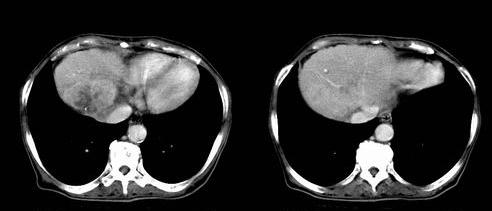

患者 女性 58岁,家族有乙肝病史,(并姊妹中已有3人确诊肝癌,真是不幸!乙肝病毒真是害死人!)近期明显消瘦,乏力,右上腹疼痛.行ct结果非常典型,请诸位老师会诊!

图片非常漂亮!肝内病灶符合较典型肝癌的强化方式,速升速降,其内可见坏死,腹膜后示肿大淋巴结融合成团,包绕腹主动脉、腹腔干动脉、肠系膜动脉。右肾小囊性病灶,未见明显强化。

地一个图是双期扫描`~~~~动脉期肿瘤强化~~静脉期肝实质强化`~肿瘤不强化`~很典型是个肝ca~~

肝脏80%左右有静脉供血~~~所以地一个强化肯定不是肝实质~~~平扫有个低密度的`~结合临床可以肯定

典型肝硬化、肝脏右后叶肝癌。动脉期、静脉期很好,不知是否用高压注射器?

很好太典型了,做的三期扫描也很漂亮啊。